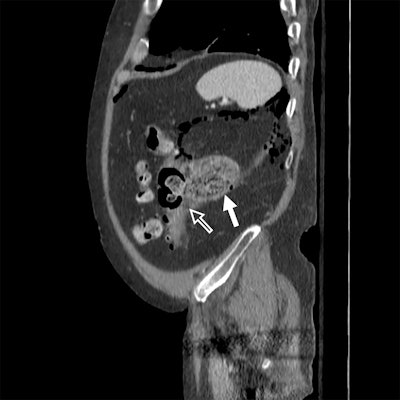

In 2015, lead author Dr. Elliot Dickerson and colleagues established semiweekly rounds of about 60 minutes in length between the on-call acute care surgery team and one of three abdominal radiologists. During these meetings, an attending surgeon outlined the current diagnostic impression and treatment plan before the group performed a comprehensive imaging review of the primary radiologic examination. Over the course of the year, 100 cases were reviewed, the most common of which were CT of the abdomen and pelvis with contrast (83 of 100 cases).